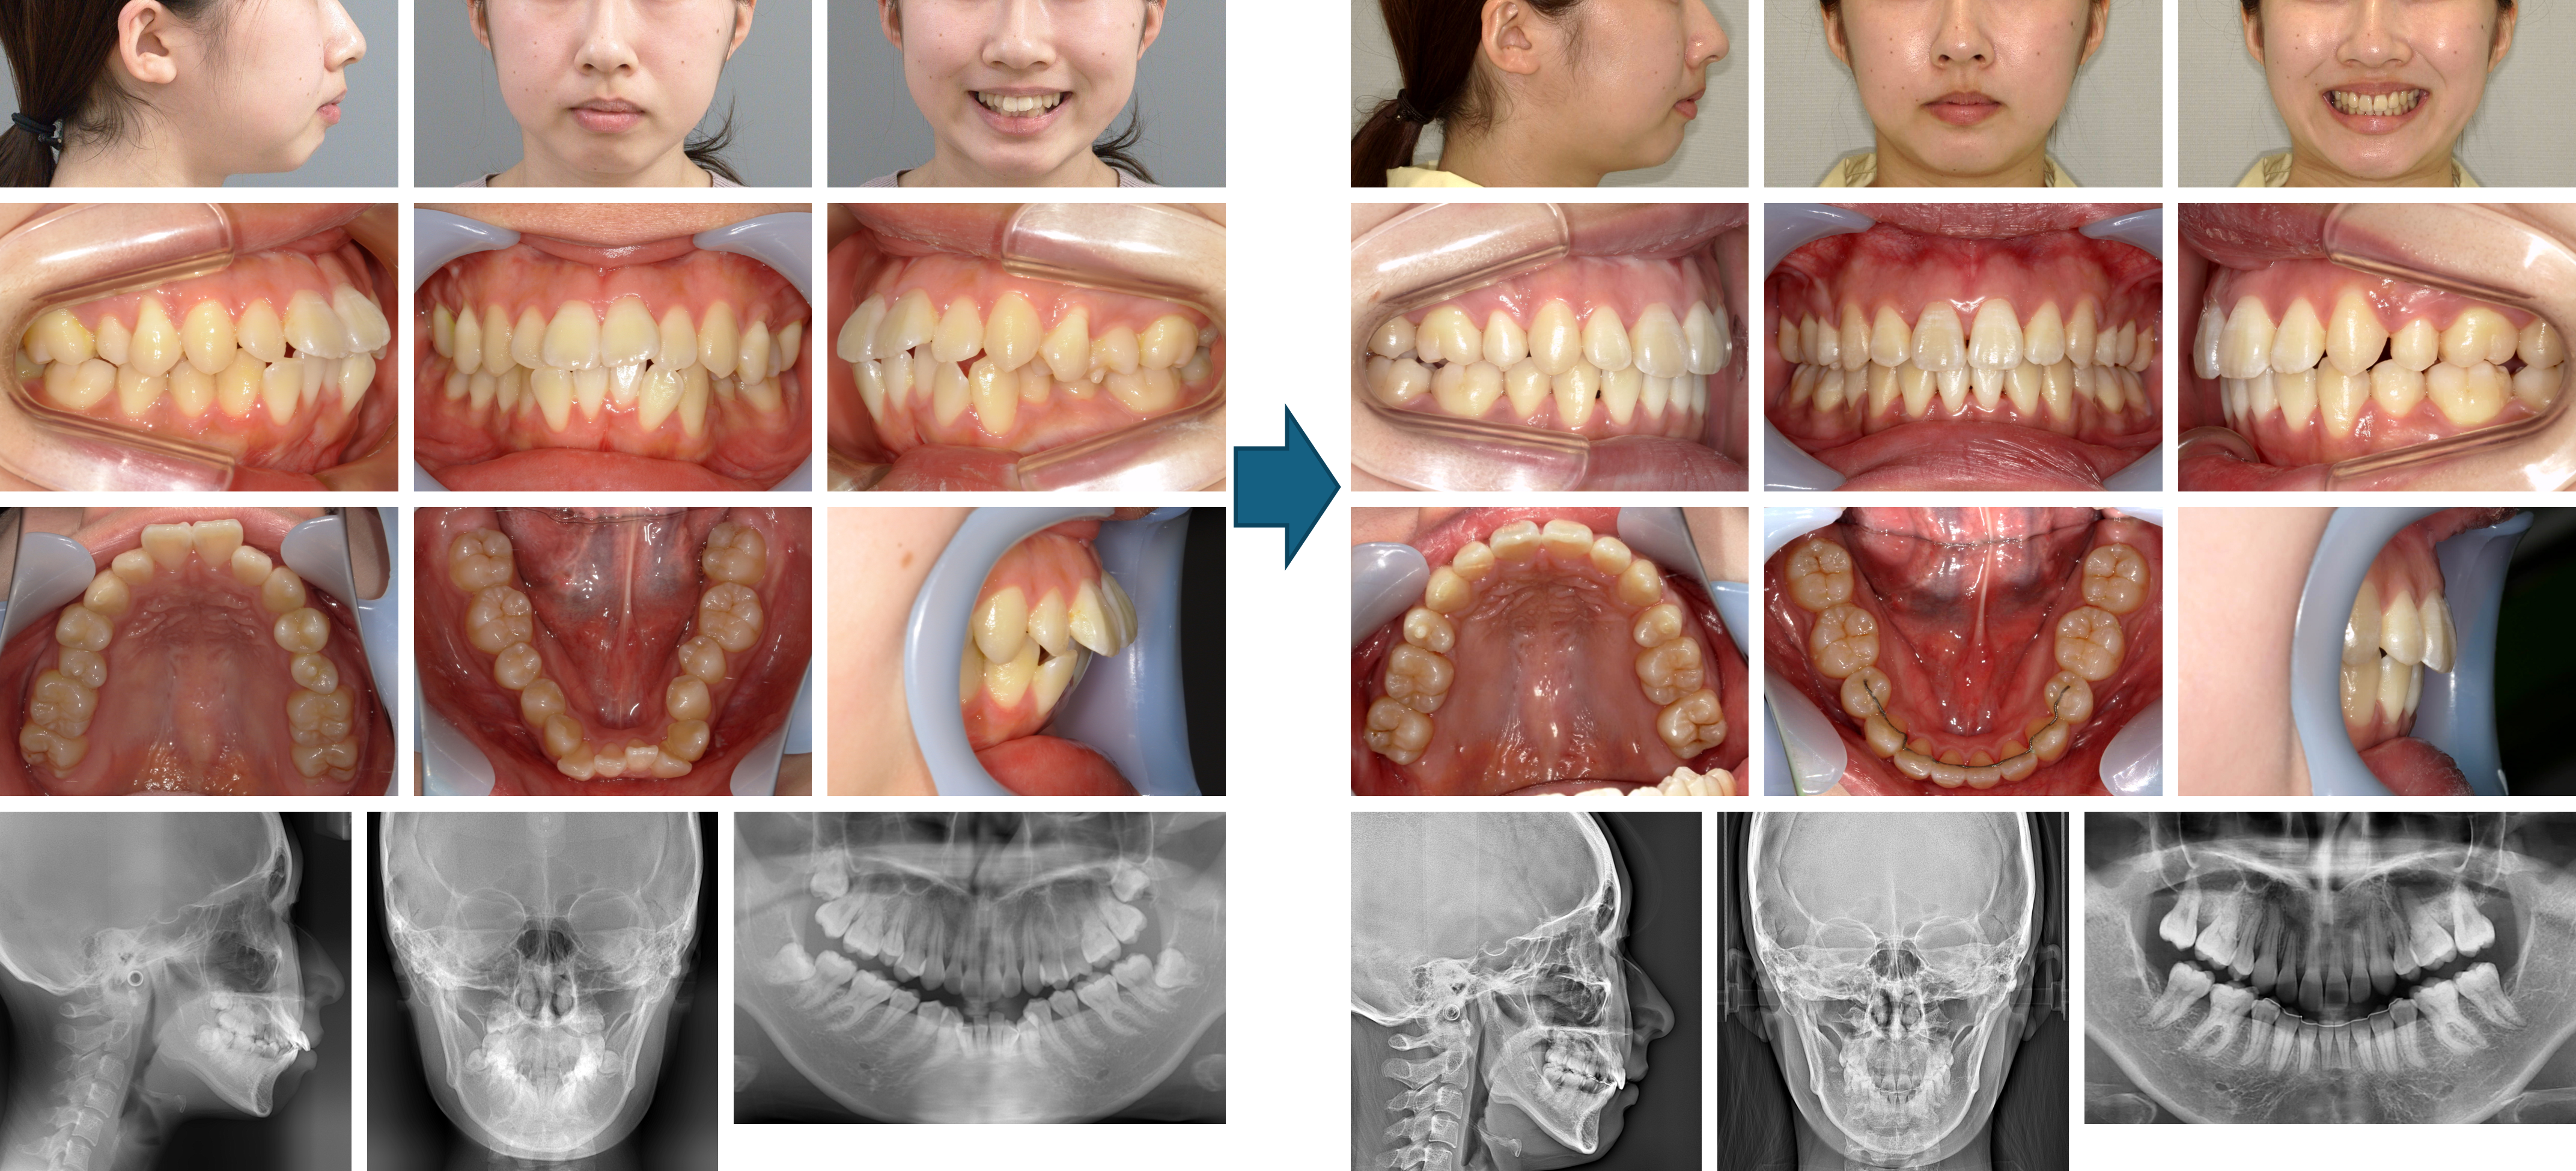

【治療例】初診時年齢:20歳1か月 / 性別:女性 / 主訴:ガタガタ、嚙み合っていない

治療の概要:他院にて学童期に受け口の改善を矯正歯科治療にて行っていたが、後戻りが徐々に生じた為来院した。噛み合わせが浅く叢生が認められた為、上下顎両側第一小臼歯抜歯を行ったのち、上下マルチブラケット装置にて顔貌及び、咬合の改善を行った。

主訴:ガタガタ、嚙み合っていない

診断名:骨格性下顎前突症例

使用した主な装置:マルチブラケット装置、顎間ゴム

抜歯/非抜歯および抜歯部位:抜歯(上下顎両側第一小臼歯)

治療期間:2年3か月

治療回数:40回

リスクの副作用:歯の移動や抜歯による違和感や疼痛、口内炎、歯肉退縮、歯根吸収が生じることがある